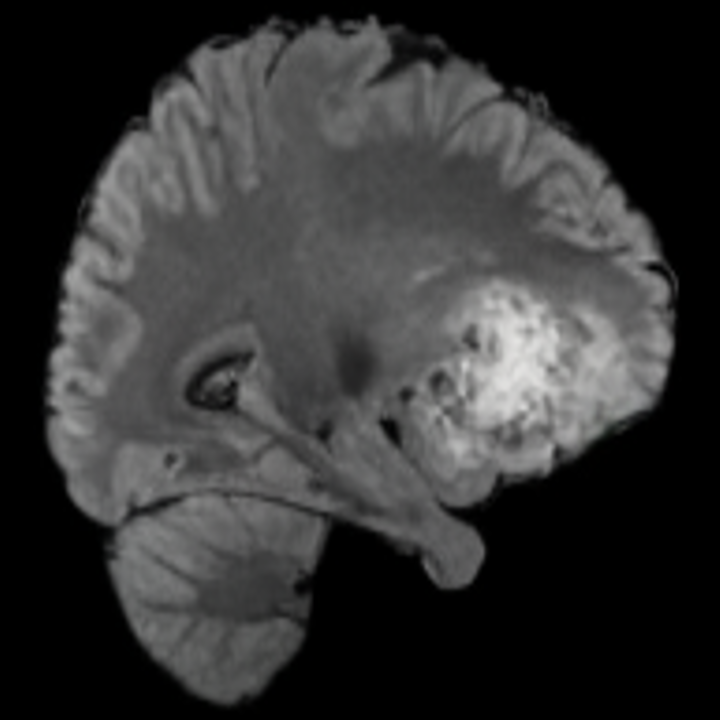

Our results unequivocally highlight the superior performance of X-Diffusion in terms of both qualitative and quantitative metrics. Representative MRI volumes generated by our pipeline, when juxtaposed with ground-truth images, showcased remarkable similarity, with even intricate physiological features like tumor information, spine curvature, and fat distribution being accurately captured.

Notably, X-Diffusion achieves sota dB for a few input slices while baselines require more than 60 input slices to achieve similar performance (Figure 7). The margin is more than 12 dB PSNR for the 1-slice input in both the BRATS and the UK Biobank benchmarks (see Table 1 and Figure 6). For reference, two randomly sampled MRIs from the UK Biobank would have a PSNR of 15.95 dB 0.36 (on 4800 randomly sampled examples). The slices from 3D reconstructed volumes at varying depths and axis of rotation visually match the ground truths (see Figures 5 and Figure 4). We also plot the error map (Figure 4) of such X-Diffusion generations to highlight the differences with the ground truth MRIs.

Tumour Information Preservation. For the brain tumor segmentation, we use a Swin UNETR model[27, 70], trained with random rotation, and intensity as data augmentation. In Figure 5, we highlight the tumor profiles of the generated MRIs compared to the ground truth tumour profile. In the test set with human ground-truth annotations (), the real MRI Dice score is 85.15 while the generated MRIs from a single slice have a dice score of 83.09. This shows how the generated MRIs indeed preserve the tumor information and can act as an affordable and informative pseudo-MRI, before conducting an actual costly MRI examination in hospitals.